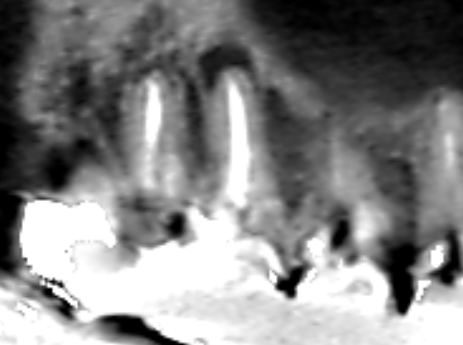

上顎第一大臼歯の近心頬側根の冠状断のCT画像です。

矢印の先の上顎第一大臼歯の近心根に膿の影がみられます。根管充填は根の先まで届いていますが、膿ができていました。